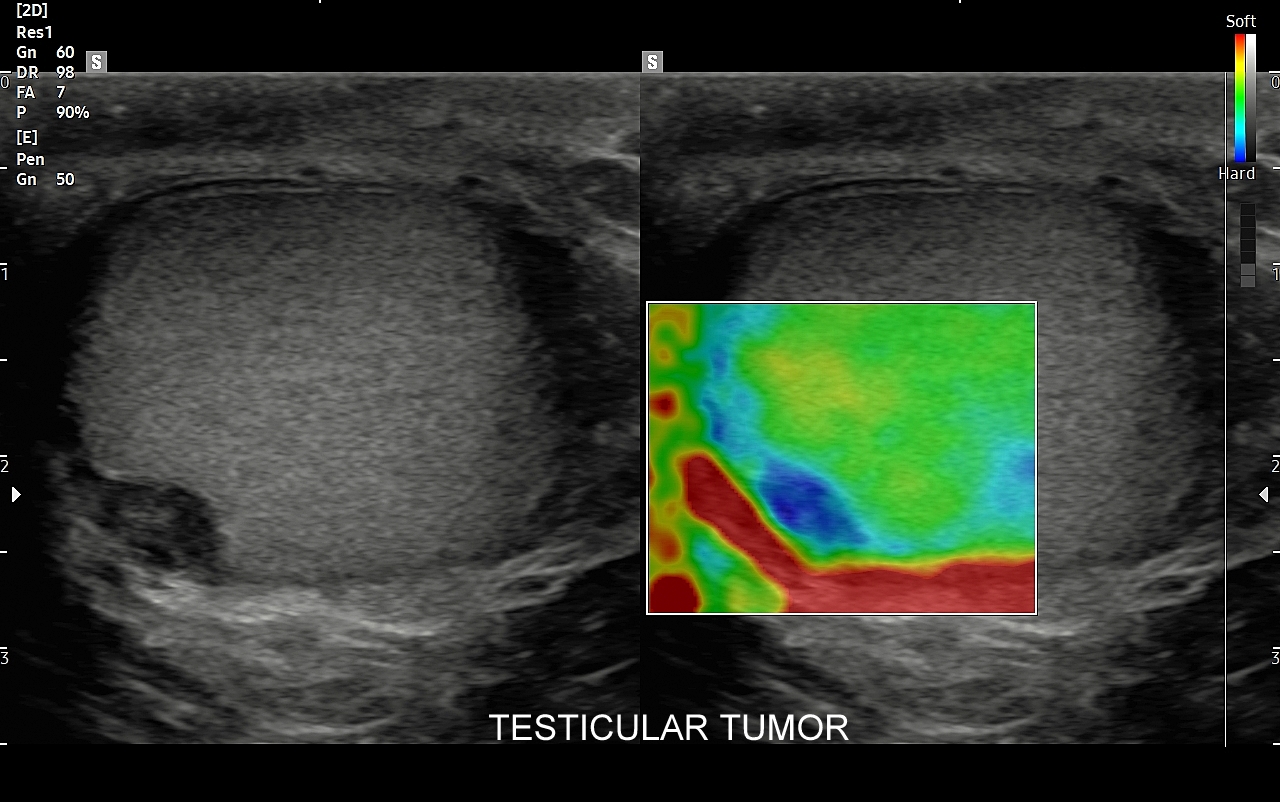

Mosznę bada się aparatem USG wyposażonym w dedykowaną sondę o wysokiej rozdzielczości przeznaczoną do oceny jąder i drobnych struktur moszny, koniecznie z zastosowaniem trybów dopplerowskich, takich jak Doppler kodowany kolorem, Doppler spektralny i obrazowanie mikrounaczynienia. Dopełnieniem badania USG jąder jest użycie w stosownych przypadkach trybu elastografii oraz trybu USG z kontrastem (CEUS). Lekarzem, który pierwszy we Wrocławiu i na Dolnym Śląsku przeprowadził badanie CEUS jąder jest dr Tomasz Szczepański.